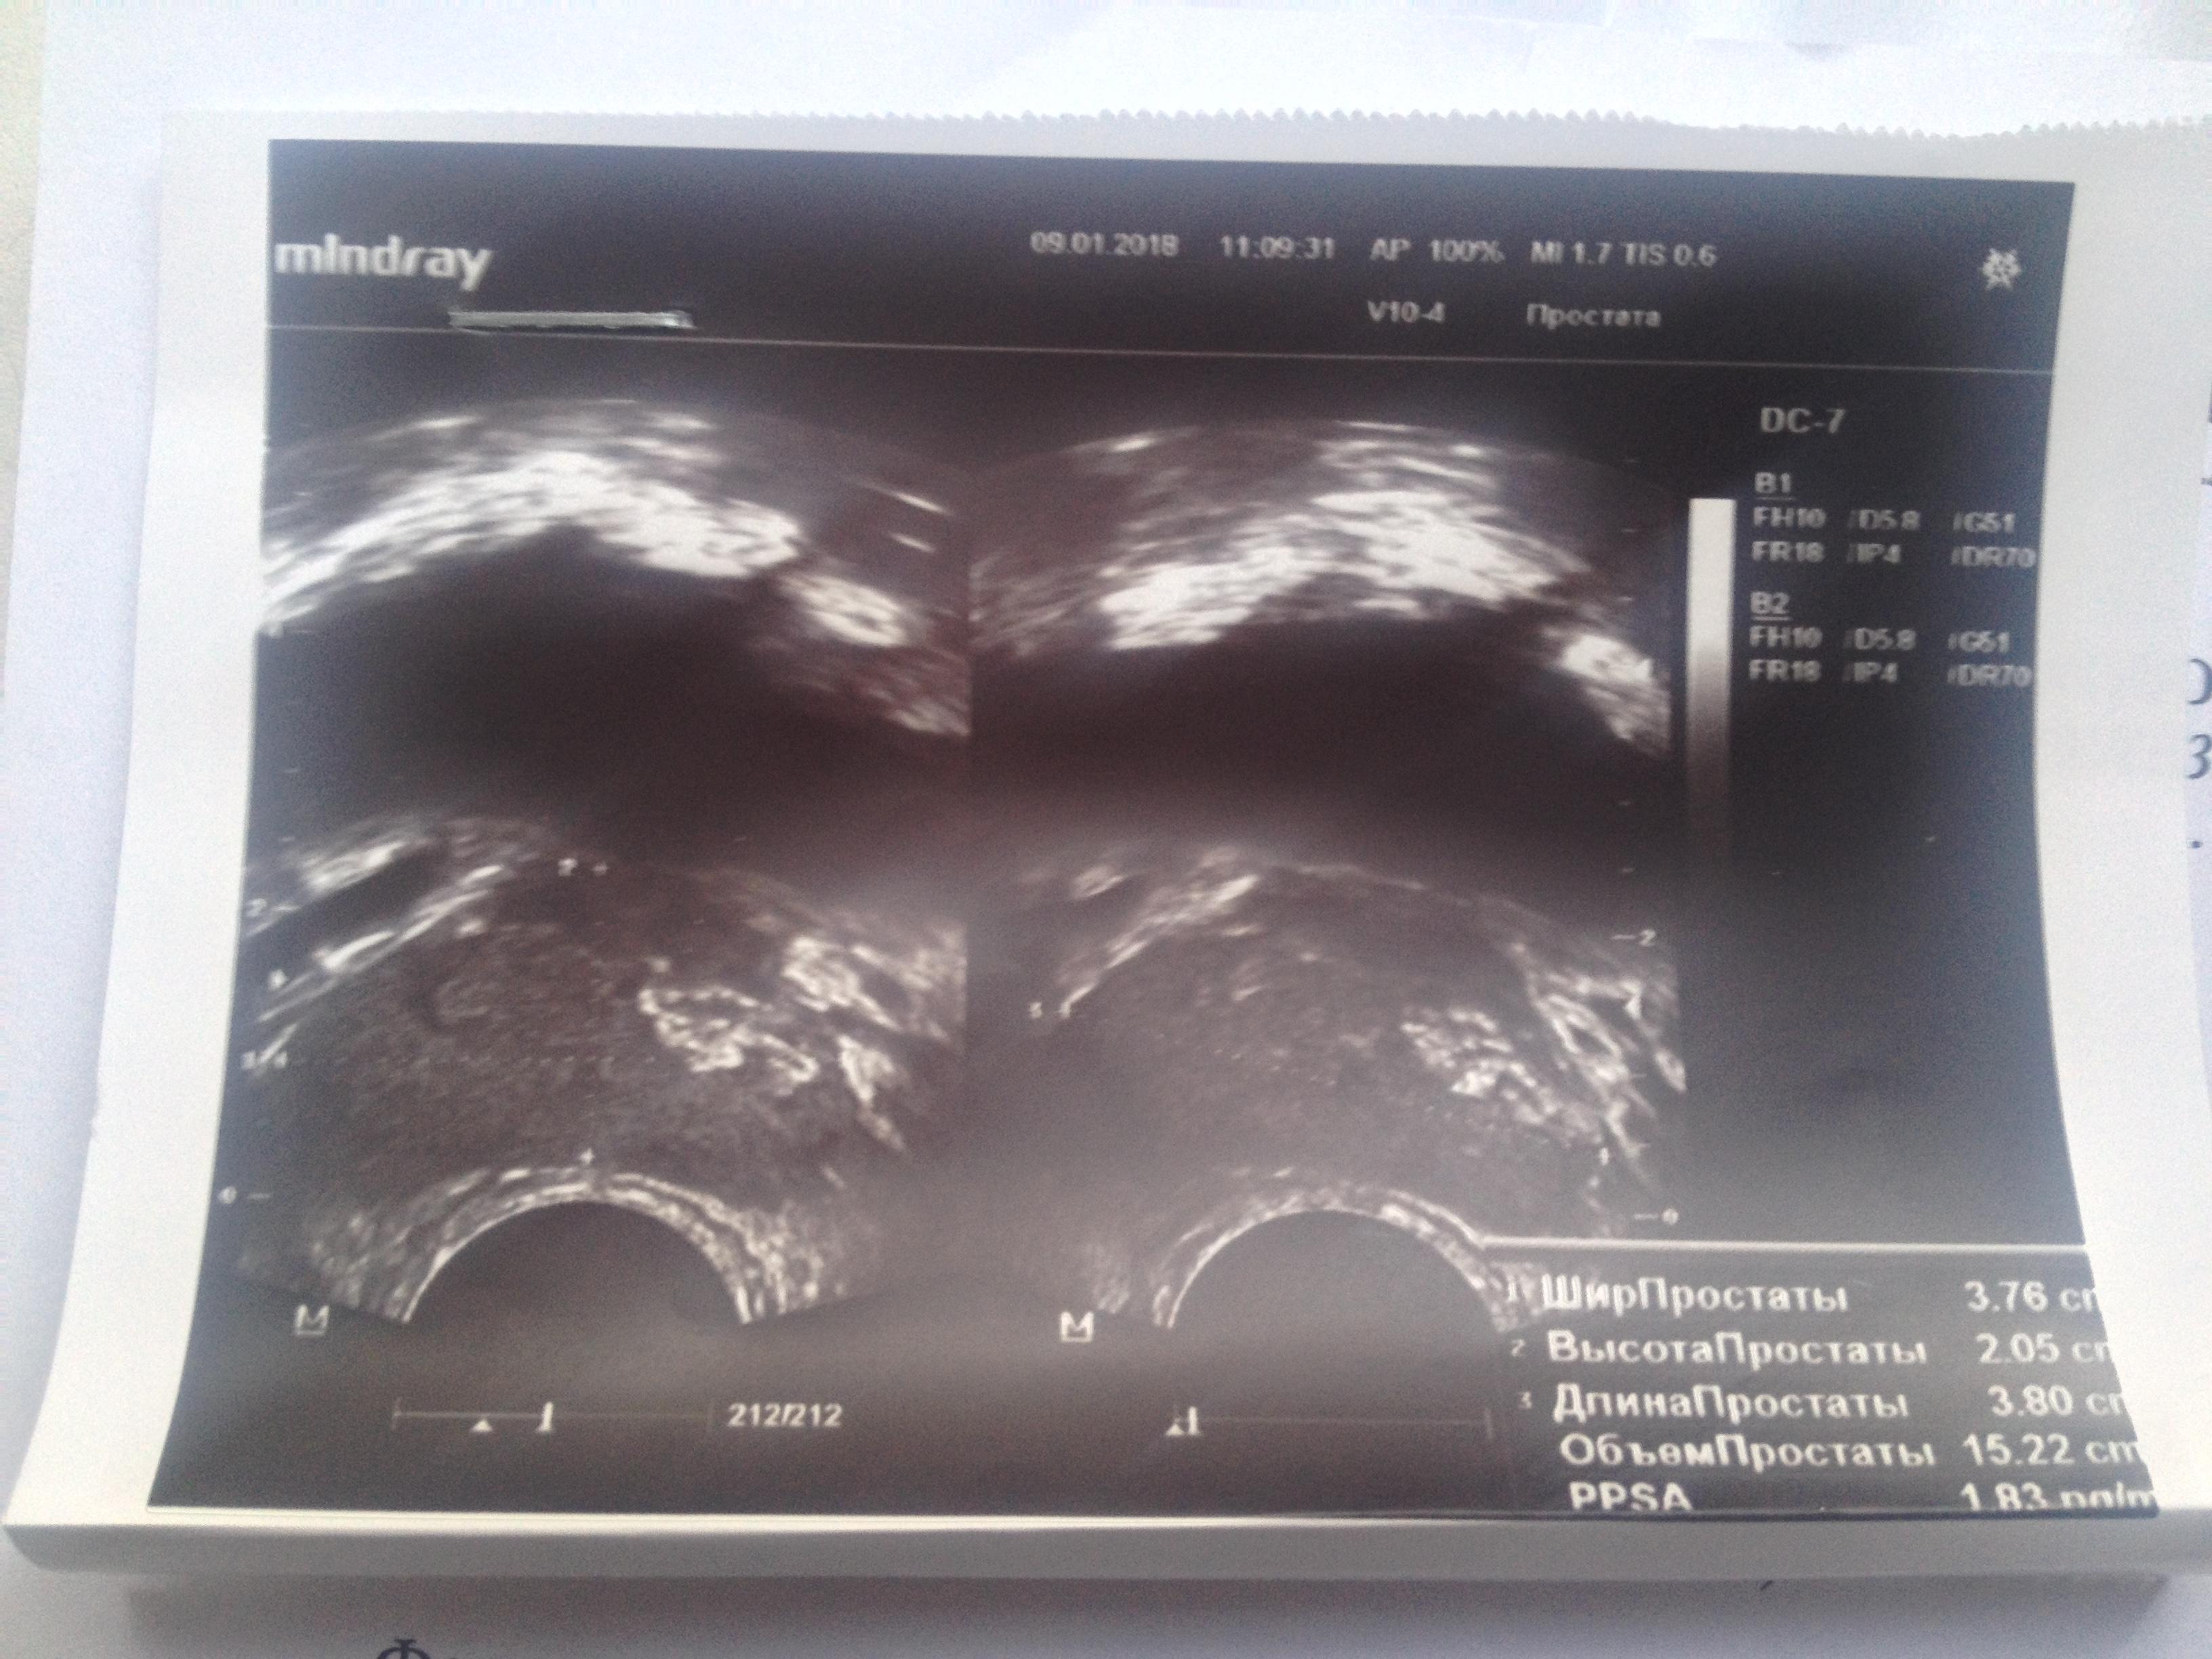

8 января пошёл на приём к урологу. Врач, произведя осмотр (крутил, вертел, сжимал пенис со всех сторон) сказал, что ничего не видит и всё c пенисом хорошо. Сказал сдать анализы и сделать ТРУЗИ предстательной железы (прикладываю фото анализов и ТРУЗИ). В итоге еще через неделю на повторном приёме, врач сказал, что было переохлаждение и как итог воспаление хронического простатита, в анализах enterococcus spp (анализы прилагаю).